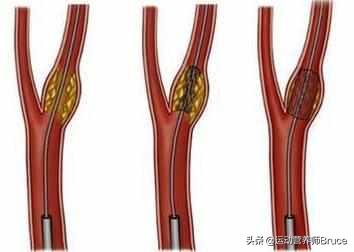

プラークが発生する過程にはいくつかの段階があり、まず血管の内皮が傷つき、血管内面の保護層が「壊れる」ようになると、血液中の高分子脂肪が低比重リポ蛋白と呼ばれる一種の物質によって血管壁の内膜中膜層に大量に運ばれて蓄積し、血管壁が肥厚し、医療では内膜中膜層が1mm以上になると動脈硬化が起こっていると言われています。内膜中膜層の肥厚が1mmを超えると、局所的に凝集して塊になったような動脈硬化、すなわち初期プラークが生じたといわれる。

初期のプラーク形成は、脂肪の蓄積が一連の炎症反応を引き起こし、実際には、脂肪は常に酸化変性、粥状物質の形成であり、これらの物質は、血管の正常な構造を破壊し、血管の一部となり、この時点で、脂質化された材料は、通常、ソフトスポットと呼ばれる液体の状態にほとんどである。

ソフトスポットの脂質化した物質は、皮膚感染症が膿を出すと線維化し痂皮化するように、時間の経過とともに壊死することがある。また、カルシウムが沈着すると石灰化が起こり、プラークが硬くなり、血管収縮機能がより低下する。このようなプラークはハードスポットと呼ばれる。

プラークが血管に与えるダメージや影響は、プラークの形成段階によって異なることがわかる。 初期のプラークは血管の構造に深刻なダメージを与えておらず、除去したり元に戻したりできる可能性があるが、ソフトプラークやハードプラークはすでに血管の正常な構造を置き換えてしまっている。プラークを完全に除去することは不可能であり、プラークの継続的な成長を止め、遅らせることが必要である。

治療後にプラークを除去できるかどうかは、プラークの病理学的病期と関係している。動脈プラークが発見された場合、超音波検査などでプラークがどのような状態にあるかを明らかにし、治療後にどのようなことが起こりうるかを把握することができます。 プラークを除去できることが最良の結果であり、プラークを除去できない場合は血管病変の進行を止めることが最善となります。